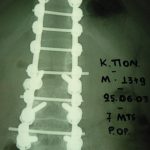

Εικ. 1: Προεγχειρητική προσθιοπίσθια ακτινογραφία της θωρακο-οσφυικής μοίρας της σπονδυλικής στήλης

Παρατηρείται οστική αραίωση του δεξιού τμήματος του σώματος του 12ου θωρακικού σπονδύλου.